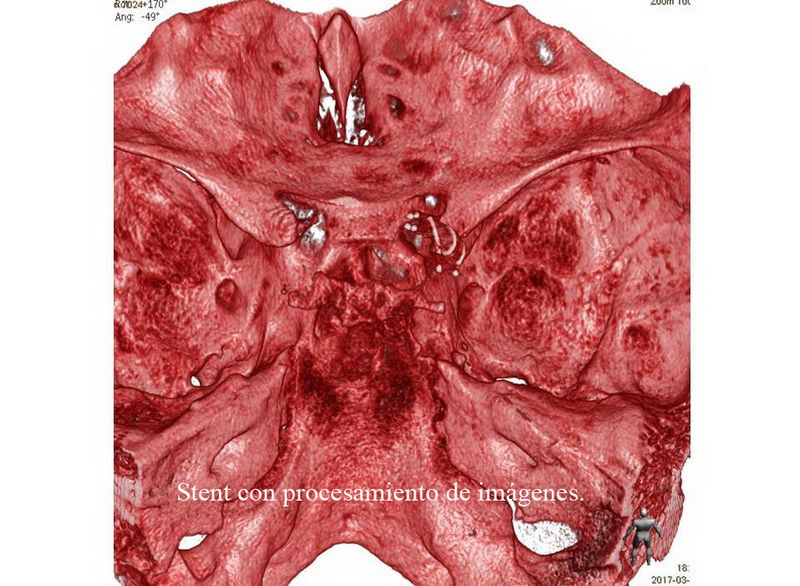

Aneurisma de cara posterior de A1